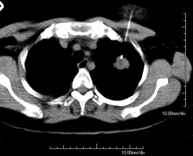

- Tórax- TC Tórax Prueba diagnóstica que consiste en obtener imágenes del tórax de alta definición anatómica (pulmones, corazón, mediastino, grandes vasos, caja torácica, etc.) mediante el empleo de un equipo de TC (Tomografía Computarizada). Dichas imágenes se estudian posteriormente en una estación de trabajo que permite reconstrucciones bidimendionales en diferentes planos del espacio y también reconstrucciones 3D (volumétricas). Algunos estudios requieren el empleo de contraste yodado para mejorar la definición de las imágenes. Prueba diagnóstica que consiste en obtener imágenes del tórax de alta definición anatómica (pulmones, corazón, mediastino, grandes vasos, caja torácica, etc.) mediante el empleo de un equipo de TC (Tomografía Computarizada). Dichas imágenes se estudian posteriormente en una estación de trabajo que permite reconstrucciones bidimendionales en diferentes planos del espacio y también reconstrucciones 3D (volumétricas). Algunos estudios requieren el empleo de contraste yodado para mejorar la definición de las imágenes.

- Angio-TC Aorta torácica Prueba diagnóstica que consiste en el estudio de la aorta torácica (principal arteria del tórax) mediante el empleo de un equipo de TC (Tomografía Computarizada). Esta técnica requiere el empleo de contraste yodado, y proporciona imágenes de alta definición anatómica. El uso del TCMD (TC Multidetector) acorta el tiempo de exploración, disminuye la dosis de radiación y mejora la calidad de la imagen. Gracias a los múltiples detectores, en determinados estudios se puede acoplar la obtención de la imagen con el latido cardíaco, técnica que permite el estudio de la válvula aórtica y de la raíz de la arteria aorta (primeros centímetros), donde el latido del corazón suele provocar múltiples artefactos de movimiento. Prueba diagnóstica que consiste en el estudio de la aorta torácica (principal arteria del tórax) mediante el empleo de un equipo de TC (Tomografía Computarizada). Esta técnica requiere el empleo de contraste yodado, y proporciona imágenes de alta definición anatómica. El uso del TCMD (TC Multidetector) acorta el tiempo de exploración, disminuye la dosis de radiación y mejora la calidad de la imagen. Gracias a los múltiples detectores, en determinados estudios se puede acoplar la obtención de la imagen con el latido cardíaco, técnica que permite el estudio de la válvula aórtica y de la raíz de la arteria aorta (primeros centímetros), donde el latido del corazón suele provocar múltiples artefactos de movimiento.

- Angio-TC Arterias pulmonares (Estudio TEP, Tromboembolismo Pulmonar) Prueba diagnóstica que consiste en el estudio de las arterias pulmonares mediante el empleo de un equipo de TC (Tomografía Computarizada) obteniendo imágenes bi y tridimensionales. En este estudio es imprescindible el uso de contraste yodado, el cual permitirá una mejor definición anatómica. Esta prueba está principalmente indicada en los casos de sospecha de tromboembolismo pulmonar (TEP) para descartar o confirmar la presencia de coágulos sanguíneos en el interior de las arterias. Prueba diagnóstica que consiste en el estudio de las arterias pulmonares mediante el empleo de un equipo de TC (Tomografía Computarizada) obteniendo imágenes bi y tridimensionales. En este estudio es imprescindible el uso de contraste yodado, el cual permitirá una mejor definición anatómica. Esta prueba está principalmente indicada en los casos de sospecha de tromboembolismo pulmonar (TEP) para descartar o confirmar la presencia de coágulos sanguíneos en el interior de las arterias.